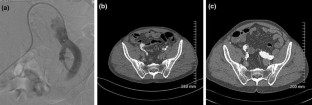

Fig. 1